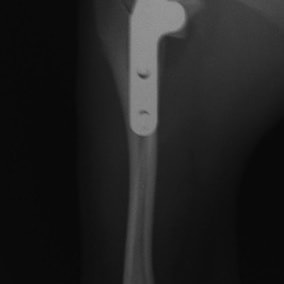

Fixin T字プレート使用して固定

・術後レントゲン

手術前TPA 28.4° が術後TPA 11.7° に矯正されました。

術前TPA計測

手術前

術後TPA計測

手術後

当院ではFixinmicroプレートを使用して小型犬のTPLO手術を実施しております。